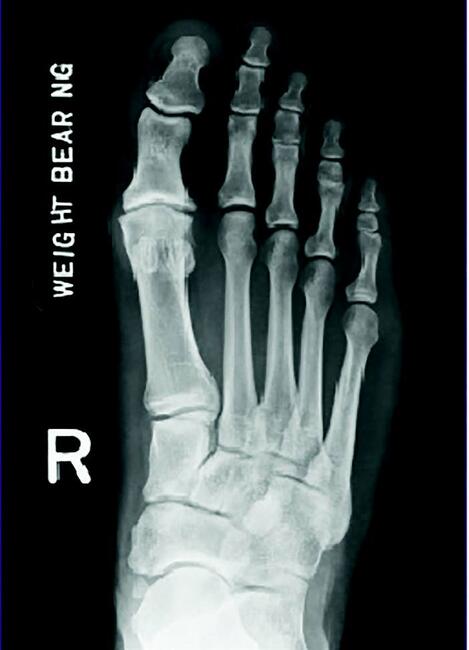

It is important to order the proper diagnostic testing in conjunction to one’s examination. We always begin with standard radiographs (full weight-bearing anterior-posterior, medial oblique and lateral). Adding in a sesamoid axial view is not a bad idea to look at the position and quality of the sesamoid complex. What I look for in radiographs is the position of the metatarsal, the degree of joint space narrowing and the degree of spur formation. What is the quality of the great toe joint? However, don’t forget to also check the overall position and alignment of the foot.

What I have realized is that with standard radiographs alone, I miss a significant amount of diagnostic information that led me to some suboptimal results. I feel this may have proven avoidable if I had additional information. I thought some cases were simple cheilectomy procedures that I later found that osteochondral lesions primarily caused the pain. Others seemed to have smooth and fluid motion in the central aspect of the joint, which ended up having far worse arthritic changes than I expected when I opened the joint. The question is; how can we know the quality of the joint and the health of the cartilage and bone prior to surgery?

CT is, in my observation, overall a great exam to show anatomic position of the metatarsal, the level of dorsal spurring, and the actual jamming angle of the joint. A weight-bearing CT is preferrable, as I feel this gives true positional information. What I prefer to use more often is an MRI of the great toe joint. I find it more useful to help me diagnose osteochondral damage, subchondral damage to the metatarsal head, and to check the overall quality of the cartilage prior to surgery. This helps me plan my procedure and avoid an intraoperative surprise.